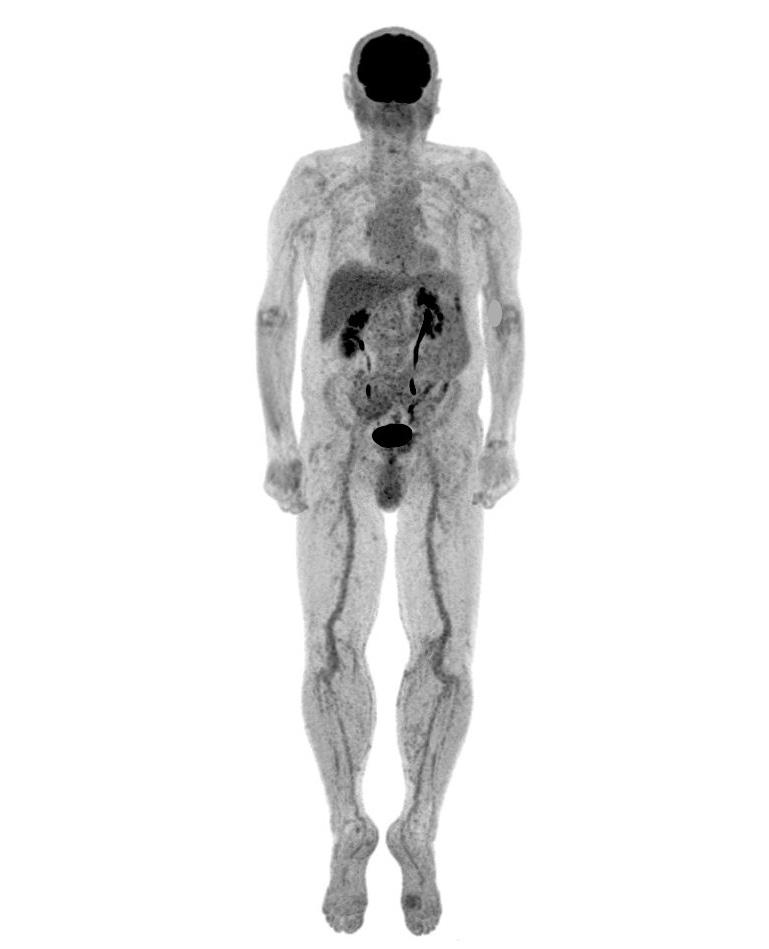

TEP-SCAN

Tomoscintigraphie par émissions de positons

La TEP-scan (Tomographie par Emission de Positons couplée à un scanner) est un examen d’imagerie médicale performant qui s’intéresse au fonctionnement, au métabolisme et à l’anatomie des organes.

Cet examen intervient dans différents domaines (cancérologie, rhumatologie, orthopédie, médecine interne) et peut permettre de détecter un cancer ou ses métastases, une inflammation ou une infection, d’évaluer la présence ou l’étendue d’une maladie, comme le cancer ou certains rhumatismes. Il pourra aussi permettre au médecin prescripteur de choisir un traitement adapté à votre maladie et / ou d’en évaluer l’efficacité et aussi de prouver une guérison.

Pour la réalisation des images, vous serez allongé sur le dos sur la table d'examen. L’appareil comporte un anneau, un peu plus large que celui d’un scanner, dans lequel la table d’examen va avancer afin de réaliser des images de votre corps, en général de la tête jusqu’à mi-cuisse, pendant environ 12 minutes.